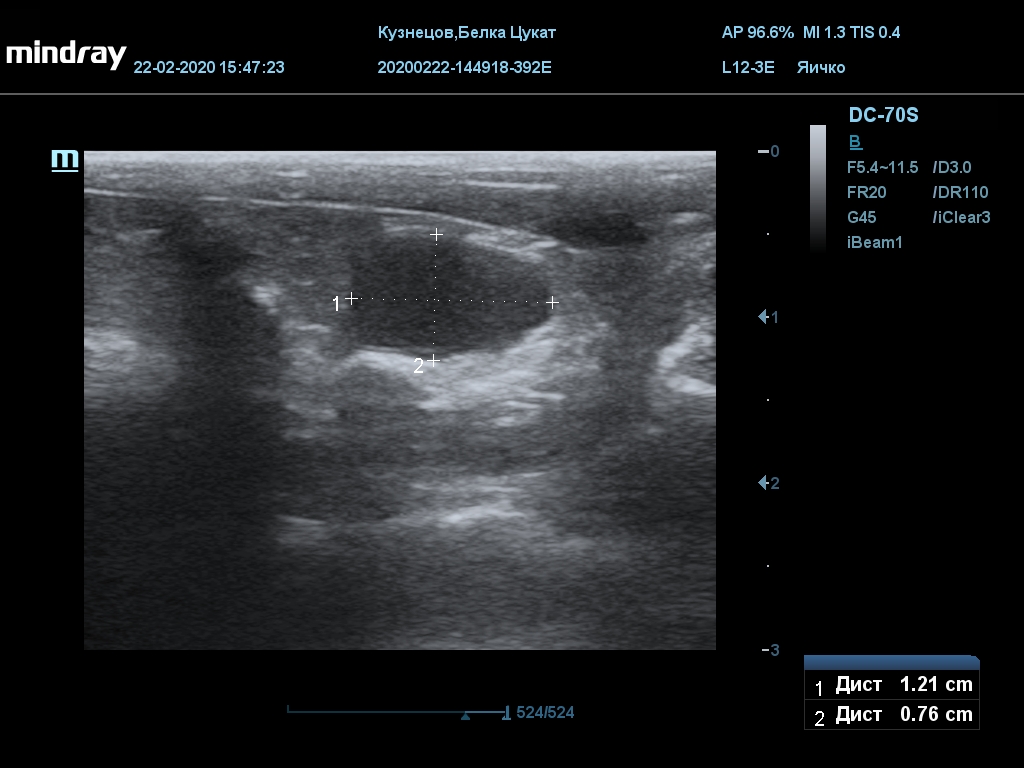

УЗИ

(почки, мочевой пузырь и, предположительно, простата)

Обращаю внимание, что делала УЗИ и писала заключение узист, которая специализируется на кошках и собаках, поэтому она сделала узи и описала, как смогла, но тонкостей грызунячьей анатомии она не знает.

Приложил только фото, есть ещё пара видео, но не знаю, как тут выложить, и надо ли.

Мочевой пузырь объём 12,1 х 7,6 х 11 мм. Стенка не утолщена, 0,5 мм, содержимое не однородное, до половины объёма гипоэхогенная мелкодисперсная взвесь. Макс. размер включений 0,8 мм. Теней нет.

Каудальнее мочевого пузыря визуализируется округлая структура размером 11,1 х 8,3 мм с ровными контурами гипоэхогенная однородная, с признаками васкуляризации.

Почка левая ровная, размер 12 х 7,6 х 8,2 мм. Контур ровный чёткий. КМД отсутствует, лоханка расширена незначительно, объёмных включений не выявлено.

Почка правая ровная, контур чёткий, размер 13,5 х 8,7 х 9,3 мм. Капсула визуализируется. КМД отсутствует, лоханка не расширена. Объёмные образования не выявлены.

Заключение: УЗпризнаки уролитиаза, объёмная структура каудальнее мочевого пузыря. Признаки расширения левой лоханки.

УЗИ

(почки, мочевой пузырь и, предположительно, простата)

Обращаю внимание, что делала УЗИ и писала заключение узист, которая специализируется на кошках и собаках, поэтому она сделала узи и описала, как смогла, но тонкостей грызунячьей анатомии она не знает.

Приложил только фото, есть ещё пара видео, но не знаю, как тут выложить, и надо ли.

Мочевой пузырь объём 12,1 х 7,6 х 11 мм. Стенка не утолщена, 0,5 мм, содержимое не однородное, до половины объёма гипоэхогенная мелкодисперсная взвесь. Макс. размер включений 0,8 мм. Теней нет.

Каудальнее мочевого пузыря визуализируется округлая структура размером 11,1 х 8,3 мм с ровными контурами гипоэхогенная однородная, с признаками васкуляризации.

Почка левая ровная, размер 12 х 7,6 х 8,2 мм. Контур ровный чёткий. КМД отсутствует, лоханка расширена незначительно, объёмных включений не выявлено.

Почка правая ровная, контур чёткий, размер 13,5 х 8,7 х 9,3 мм. Капсула визуализируется. КМД отсутствует, лоханка не расширена. Объёмные образования не выявлены.

Заключение: УЗпризнаки уролитиаза, объёмная структура каудальнее мочевого пузыря. Признаки расширения левой лоханки.